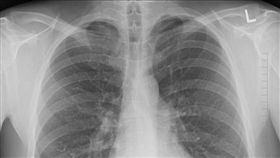

肺癌轉移有解 黃斑部老藥新用抑復發

國人十大癌症死亡率最高的癌症仍是肺癌,連續9年奪冠。...